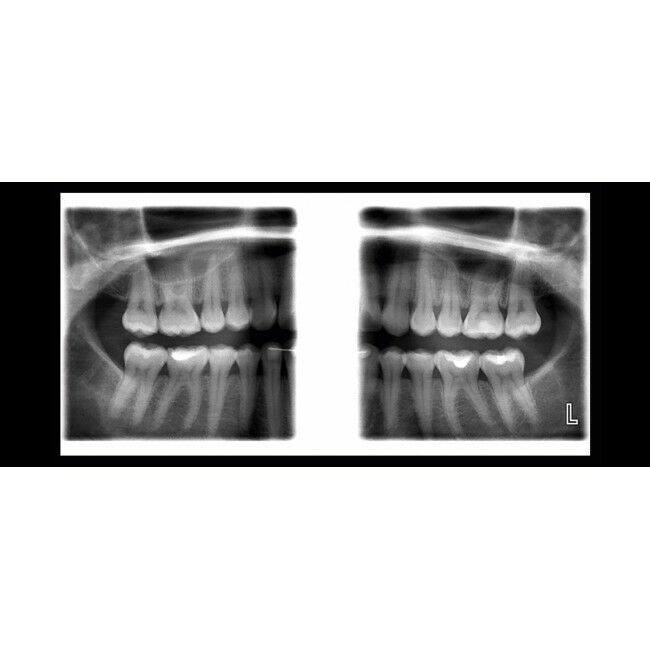

Горизонтальное и вертикальное сегментирование

Межпроксимальная панорамная

Ортогональная (перио) панорамная

Прикусная панорамная